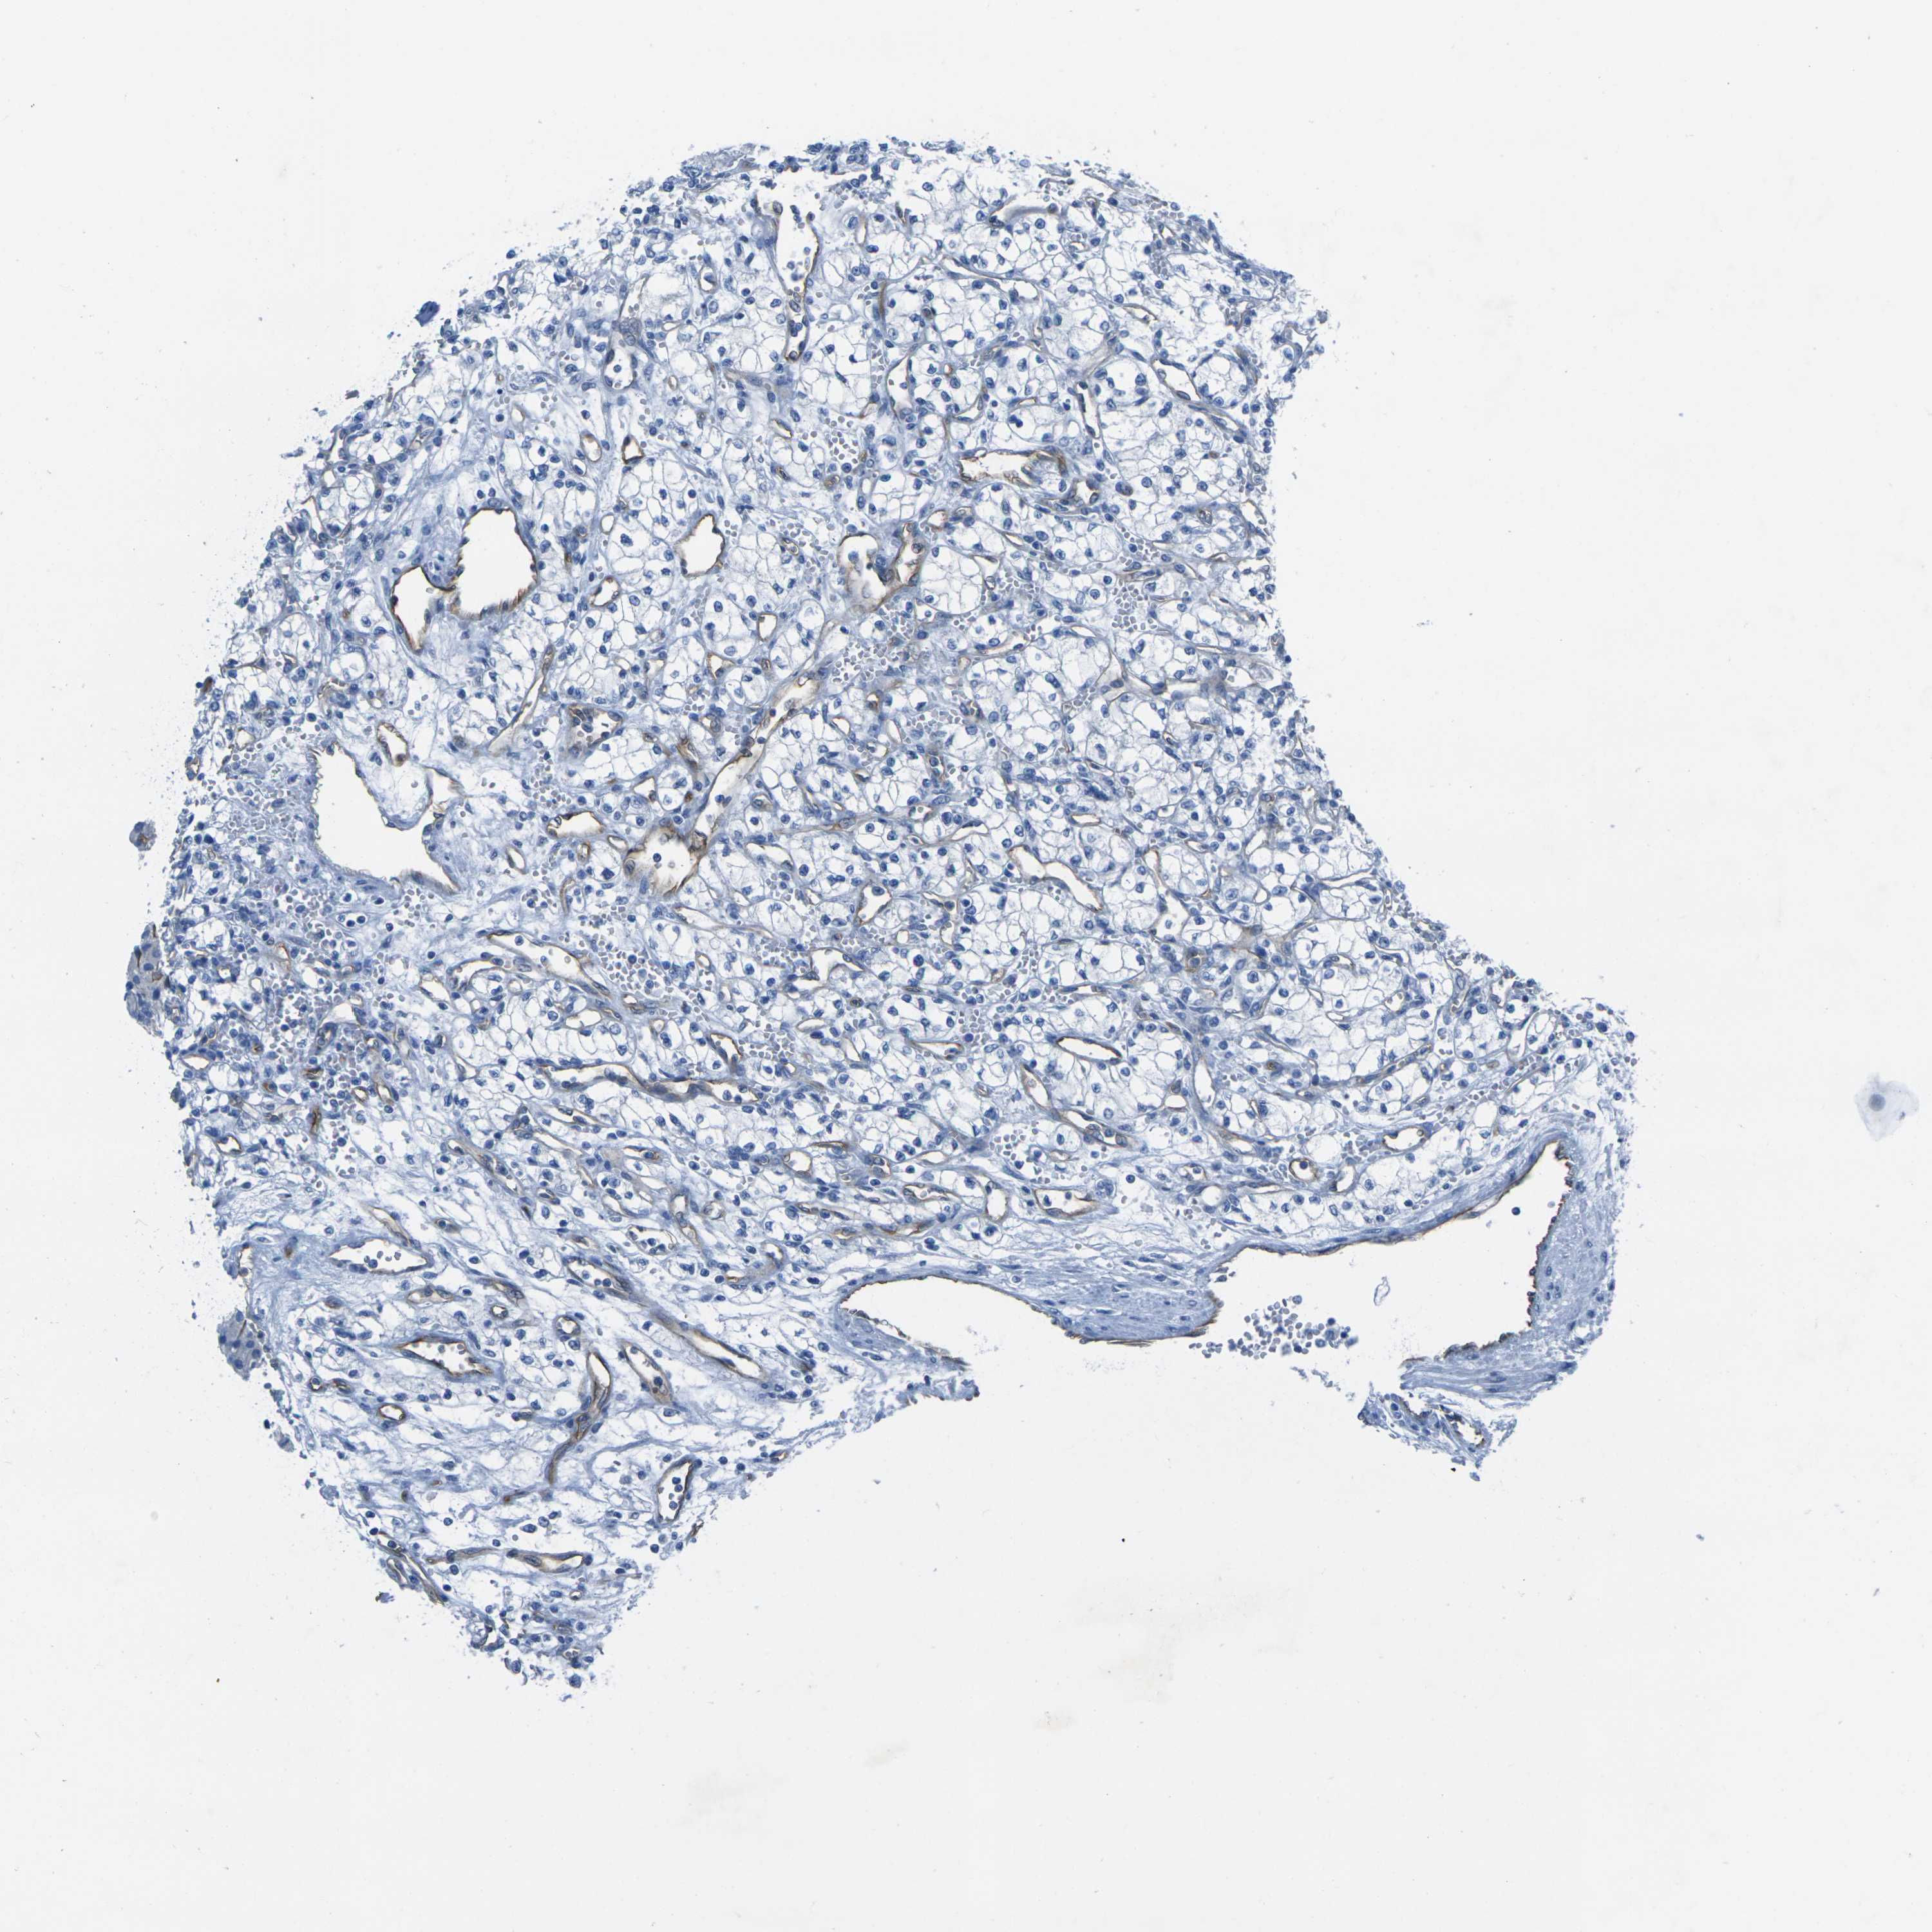

KIDNEY RENAL PAPILLARY CELL CARCINOMA (TCGA) - Interactive survival scatter ploti

The Survival Scatter plot shows the clinical status (i.e. dead or alive) for all individuals in the patient cohort, based on the same data that underlies the corresponding Kaplan-Meier plots. Patients that are alive at last time for follow-up are shown in blue and patients who have died during the study are shown in red.

The x-axis shows the expression levels (FPKM) of the investigated gene in the tumor tissue at the time of diagnosis. The y-axis shows the follow-up time after diagnosis (years). Both axes are complimented with kernel density curves demonstrating the data density over the axes. The top density plot shows the expression levels (FPKM) distribution among dead (red) and alive patients (blue). The right density plot shows the data density of the survived years of dead patients with high and low expression levels respectively, stratified using the cutoff indicated by the vertical dashed line through the Survival Scatter plot. This cutoff is automatically defined based on the FPKM cutoff that minimizes the p-score. The cutoff can be changed by dragging the vertical line or by entering a cutoff value in the square labeled "Current cut-off".

Under the Survival Scatter plot the p-score landscape (black curve; left axis) is shown together with dead median separation (red curve; right axis). Dead median separation is the difference in median mRNA expression between patients who have died with high and low expression, respectively. It is calculated as follows: median FPKM expression of dead patients with high expression - median FPKM expression of dead patients with low expression. This is intended to aid the user in visually exploring custom cutoffs and the associated p-scores and dead median separation.

Individual patient data is displayed and can be filtered by clicking on one or more of the category buttons on the top of the page. Categories describing expression level and patient information include: high, low, alive, dead, female, male and tumor stages. The scale of the x-axis can be toggled between linear and log-scale by clicking on the "x log" button. Mouse-over function shows TCGA ID, patient information and mRNA expression (FPKM) for each patient.

& Survival analysisi

Kaplan-Meier plots summarize results from analysis of correlation between mRNA expression level and patient survival. Patients were divided based on level of expression into one of the two groups "low" (under cut off) or "high" (over cut off). X-axis shows time for survival (years) and y-axis shows the probability of survival, where 1.0 corresponds to 100 percent.

HSPA12B is not prognostic in Kidney Renal Papillary Cell Carcinoma (TCGA)